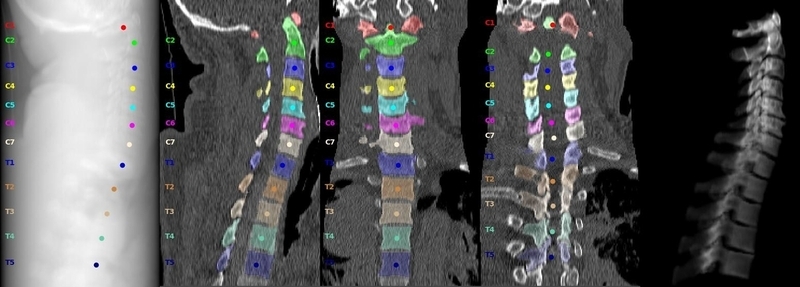

今回は教師データとしてCT撮影約2000回分、予測データとして約3000回分のデータが提示され、1回1回のデータから椎骨(頸椎の骨)部位毎の骨折有無と椎骨全体での骨折有無を予測する事が求められました。この1回分のデータ中には身体の上下方向に輪切りにされた頸椎断面の画像が数百枚含まれており、このある1回のCT撮影画像全体のことをStudy、その中に含まれる1枚1枚の頸椎断面画像をImageと呼びます。椎骨はC1(最も頭側の骨)からC7(最もお尻側の骨)という7つの骨で構成されているため、椎骨全体と併せてひとつのStudyに対し8項目の2値分類問題を行うイメージです。

RSNAコンペの実データではなく公開データセットVerse2022の画像を引用。https://creativecommons.org/licenses/by/4.0/

また、追加データとして一部のStudyには椎骨の位置をセグメンテーションしたマスク画像または骨折の位置をアノテーションしたバウンディングボックスがImage単位で付与されていました。ただし、椎骨マスク画像は学習データ約2000Study中87回分、骨折バウンディングボックスは約2000Study中235回分のみとStudy全体のうちごく少数のデータにしか付与されておらず、これらの追加データを効率良く扱う事がスコア向上を目指す上で重要なポイントでした。